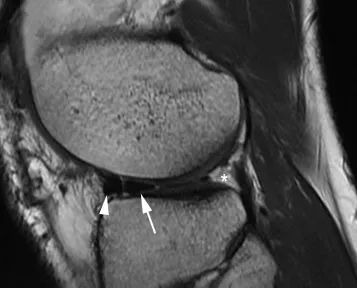

La constatation la plus fréquente est la visualisation directe des fragments migrant dans la région intercondylienne : le repère du 'double ligament croisé postérieur (PCL)' est caractéristique lorsque le ménisque médial est lésé et que le ligament croisé antérieur est intact.Le segment disloqué apparaît comme une bande arquée hypointense parallèle au ligament croisé postérieur normal, produisant un aspect de 'double PCL' (Fig. 7).Des cornes de râteau excessives (plus de 6 mm de taille) peuvent également refléter la présence d'une poignée de baril (Figure 8).Dans ce cas, le fragment de ménisque disloqué est attaché à la corne antérieure saine.

Figure 7 L'aspect de la poignée du ménisque médial présente un signe 'double PCL'.Vue sagittale pondérée PD avec suppression de graisse : le fragment de ménisque disloqué (flèche) se trouve sous le PCL normal (flèche) et forme l'aspect caractéristique 'double PCL'.

Figure 8 Aspect de la corne géante avant.Vue sagittale pondérée en densité de protons.La partie antérieure du fragment luxé (flèche) est rattachée à l'angle antérieur du ménisque (flèche).Notez que les coins arrière ne sont pas représentés (*).